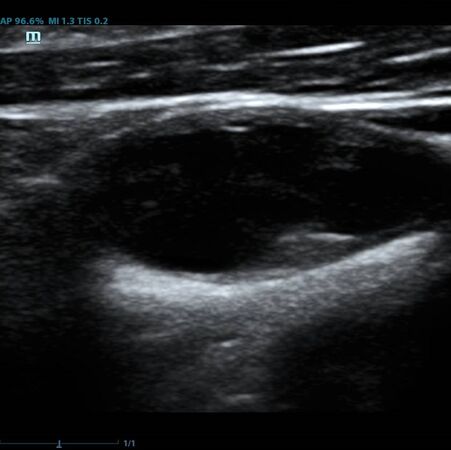

Помимо базовых целей по выявлению атеросклероза, бляшек, оценки кровотока и значимости стеноза, врачу ультразвуковой диагностики ставится и множество других задач при исследовании сонных артерий. Одна из них – оценка стабильности бляшки.

Ранее коллеги опирались на визуальную оценку, насколько бляшка гомогенная и какова её эхогенность. Есть ли в ней кальцинаты или анэхогенные участки. Для этого использовались международные классификации, с разделением среза бляшки по процентам – сколько гипер- и сколько гипоэхогенных зон. Такой метод оценки до сих пор весьма популярен, однако он имеет минусы. Основной его минус в субъективности. Тяжело на глаз сказать, на 49,9% своей площади бляшка эхогенна или же на 50,1%, да и глаз у каждого человека несколько разный. Один специалист скажет – тут больше 50% гипоэхогенного, другой, что менее. Таким образом, метод сильно зависит от оператора – специалиста ультразвуковой диагностики.

Современное решение – компьютерный анализ структуры бляшки. Ультразвуковая система экспертного класса Mindray DC-8 способна провести программный анализ полученного изображения бляшки и дать количественную оценку её структуры. Для этого используется показатель GSM – Grey Scale Median. Прибор рассчитывает медиану по показателям серой шкалы в выделенной зоне и выдает данные в виде графика распределения эхогенности и числовых данных для количественной оценки. Таким образом, исследование становится более объективным и воспроизводимым, снижается зависимость от оператора (человеческого фактора).